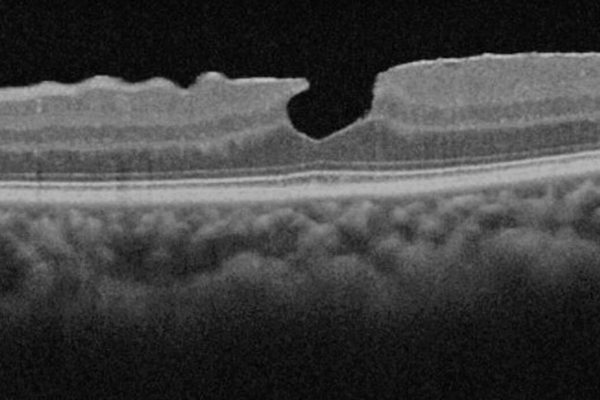

A new observation point: updating the nomenclature and classification with OCT